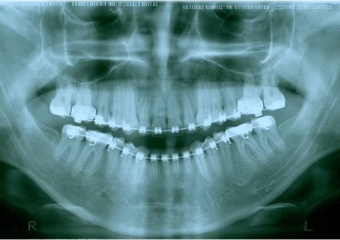

Raio x panorâmico após a cirurgia